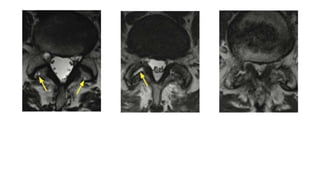

Juxtafacet (Ganglion) Cyst. T1 and T2 weighted images. A large cystic lesion arising from the anteromedial

aspect of the left facet joint. cyst appears mildly hyperintense on T2 and intermediate signal intensity on T1

intensity rim is observed on T2 weighted images. compression of the thecal sac and obliteration of the left

is seen.

Discogenic Cyst With Narrowing of the Left Lateral Recess at L4 to L5. This lesion has an intermediate

signal intensity on T1 weighted images and rim enhancement after gadolinium injection. Secondarily, there

narrowing of the left lateral recess.